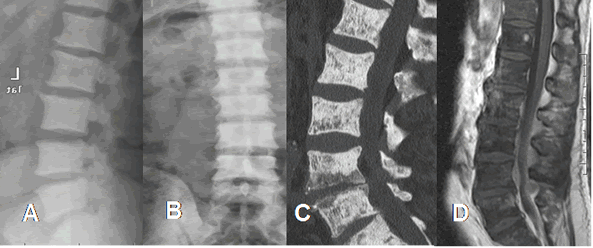

Fig 227. Metástasis mixtas.

A: TAC reconstrucción sagital en ventana de tejido, B: TAC reconstrucción sagital en ventana ósea y C: TAC axial Múltiples lesiones líticas (Flechas delgadas) y blásticas (Flechas gruesas), por neoplasia de mama.

Fig 228 A. Metástasis mixtas.

A: RM sagital en T1, B: RM sagital en T2 y C: RM sagital en STIR. Igual paciente anterior. Alteración en la señal de L2 y L4, hipointensas en T1 y T2 e hiperintensas en STIR, por metástasis mixtas de neoplasia de mama.